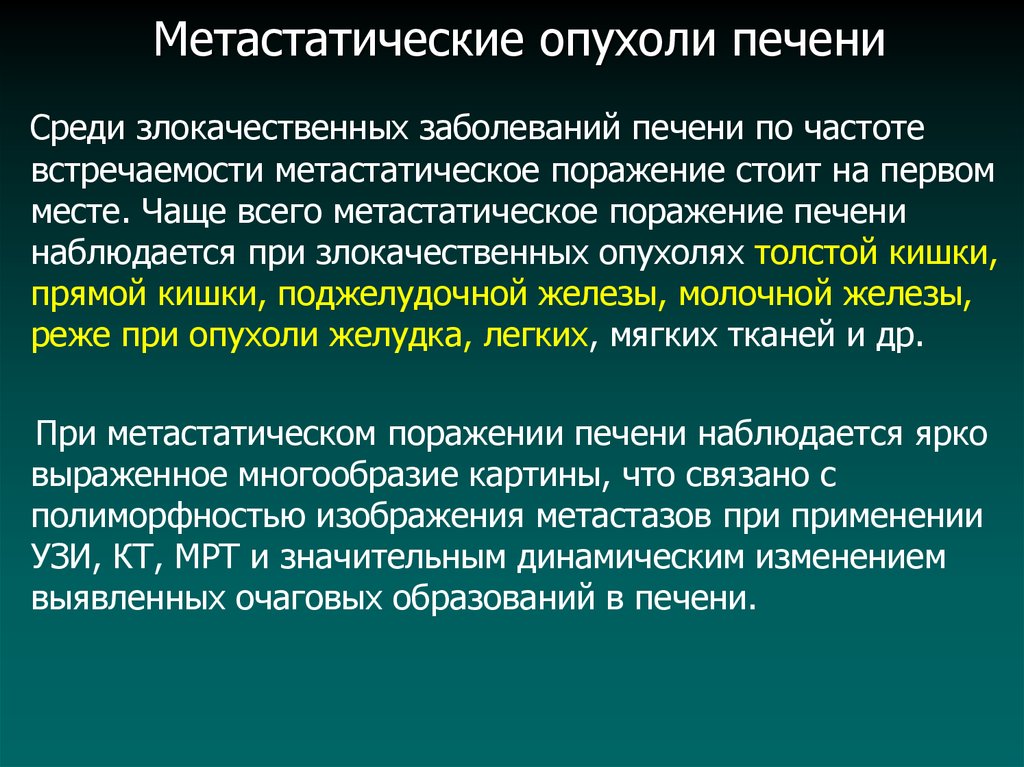

Метастатические поражения печени в ультразвуковом изображении характеризуются